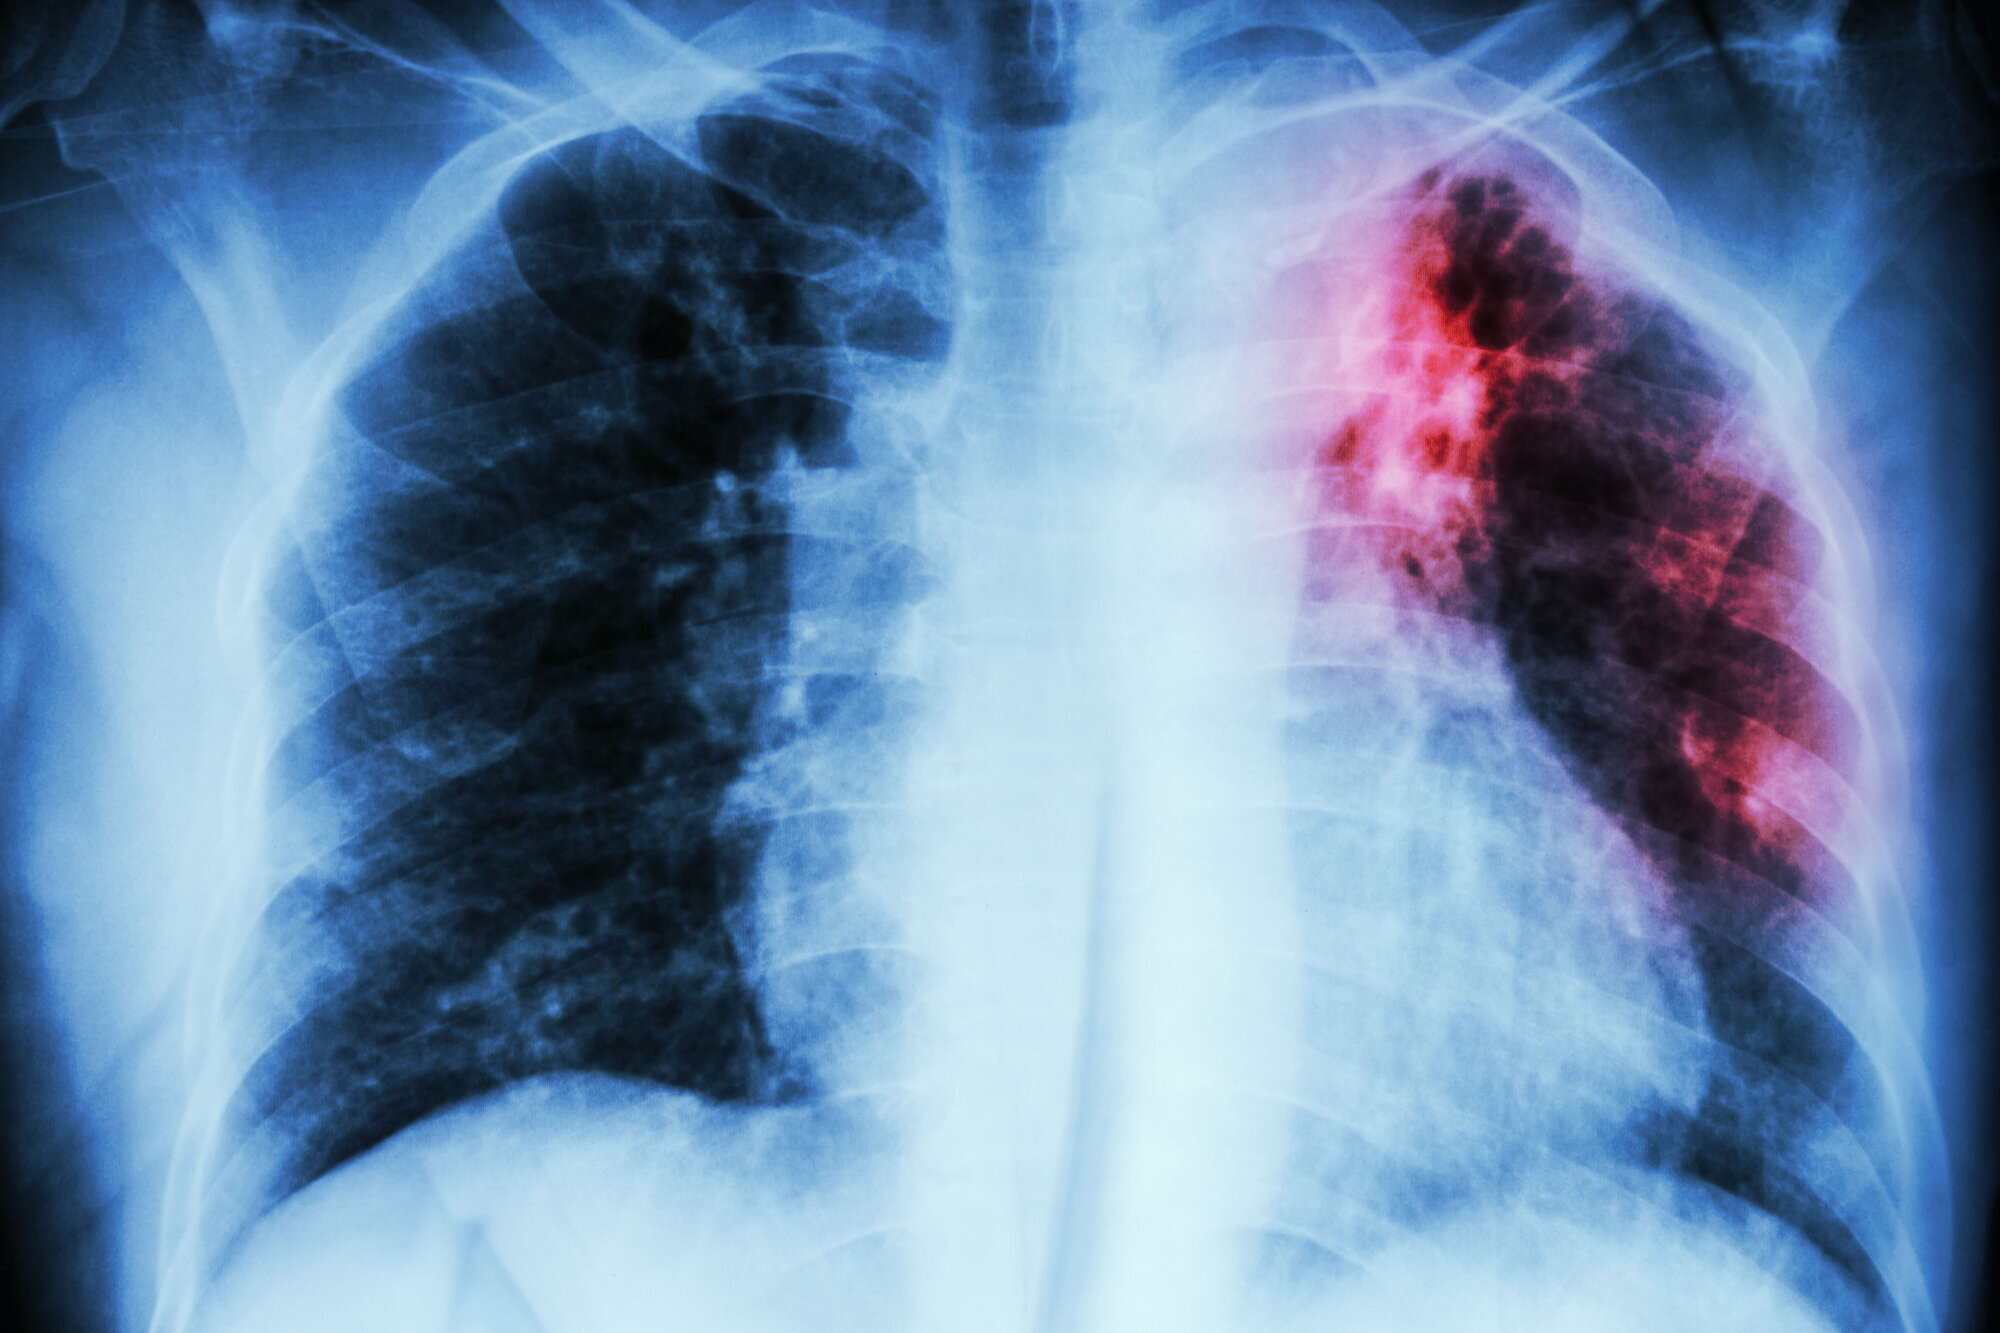

Helsepersonell med pasientkontakt har dobbelt så høy risiko for å smittes av tuberkulose som normalbefolkningen. Likevel er det ikke lenger anbefalt at de tar BCG-vaksinen.

Antallet tuberkulosesmittede i Norge gikk ned for fjerde året på rad i fjor. I 2013 fikk 392 personer tuberkulose, mens i 2017 var tallet 256. Av disse var 30 norskfødte. 16 var norskfødte med norskfødte foreldre.